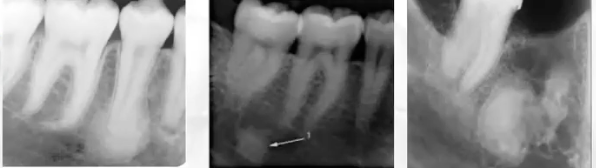

What is this

Metastatic nasopharyngeal carcinoma

What is this?

Widening of PDL and ill-defined RL seen in metastatic disease

What is this?

Metastatic small cell carcinoma of the lung

What is this?

Periapical granuloma (not to be confused with metastatic small cell carcinoma of the lung)